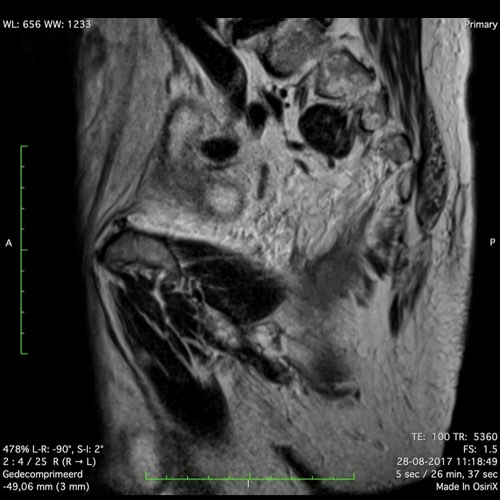

Đặc điểm MRI

- Thường khó xác định

- Thường biểu hiện nhưdày thành ruột lan tỏa, đoạn dài

- Kiểu tăng trưởng dưới niêm mạc, cho ra mộtHình ảnh “bia” (target)trên các hình ảnh cắt ngang

- Thâm nhiễm mỡ trực tràng lan tỏalà phổ biến

Hình ảnh

Các hình ảnh được cung cấp cho thấy ung thư biểu mô tế bào nhẫn với tình trạng dày lan tỏa thành trực tràng, hình ảnh bia bắn điển hình, và sự xâm lấn mỡ mạc treo trực tràng.